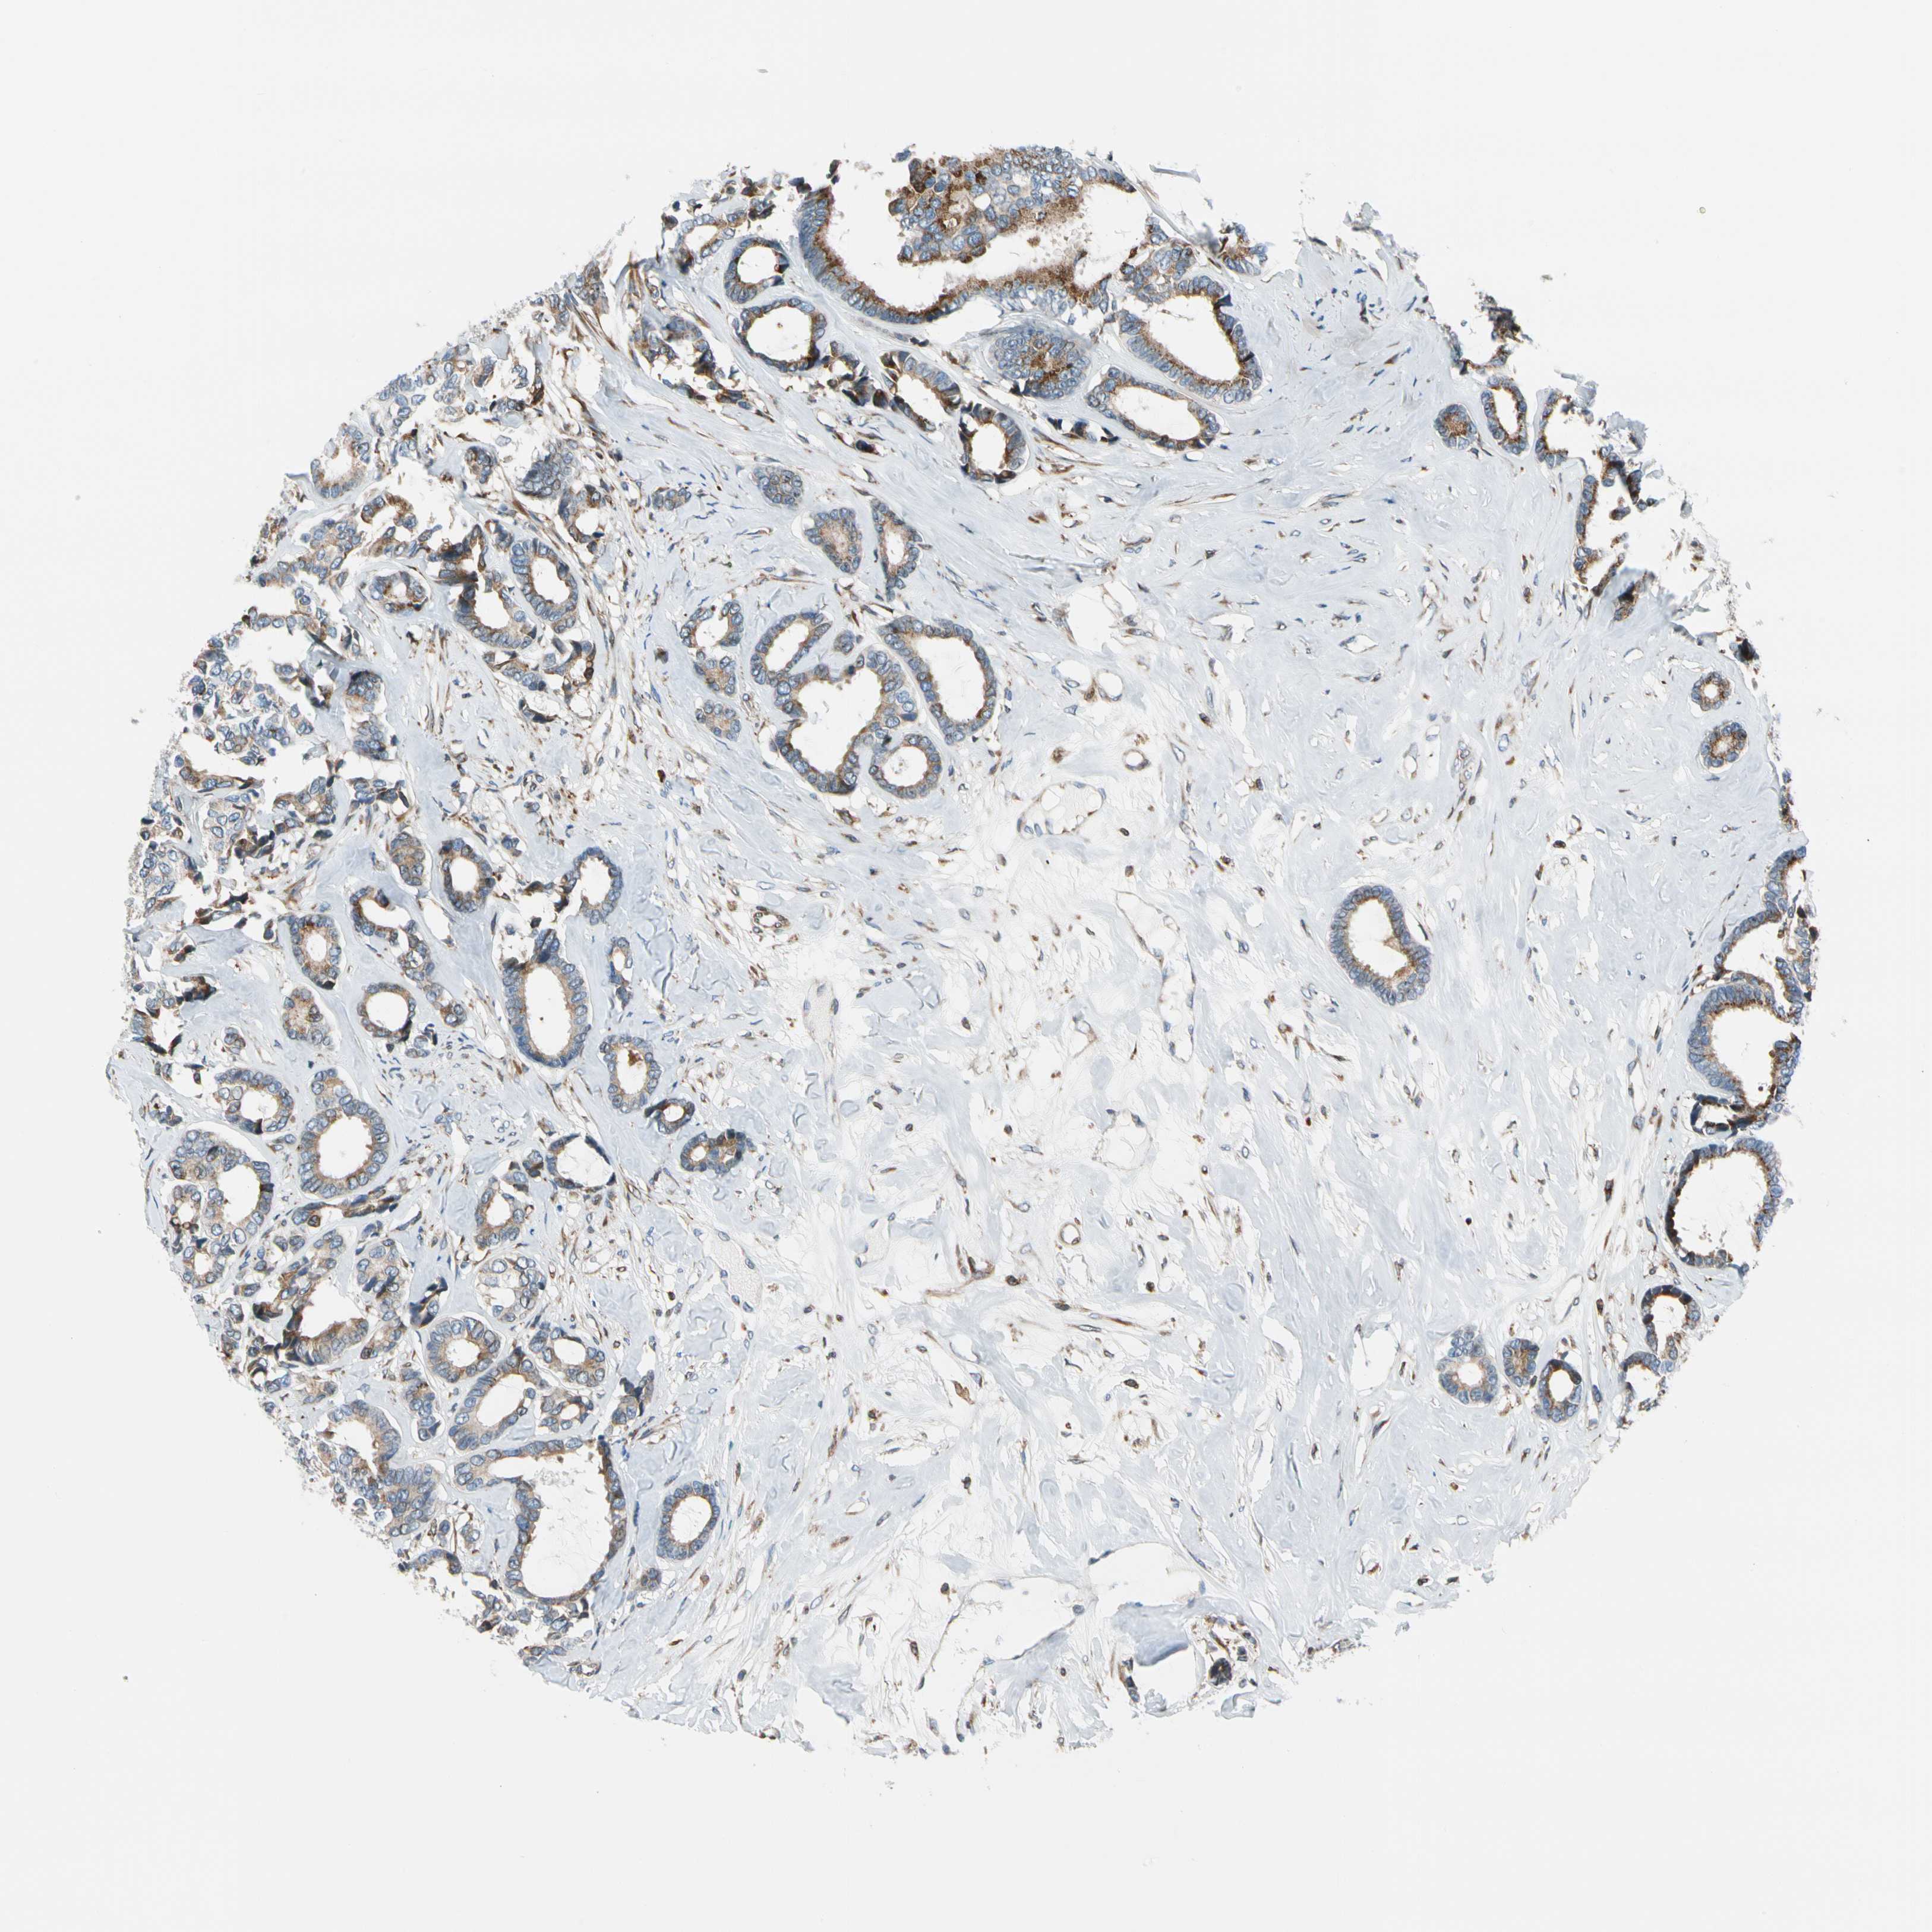

CANCER BREAST CANCER Show tissue menu

Breast cancer

Human cancer